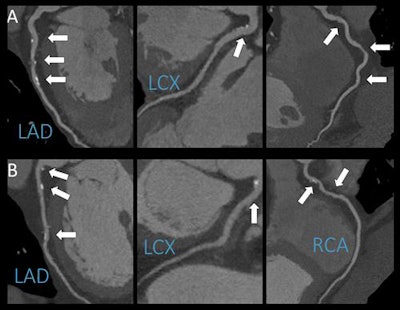

The group used coronary CT angiography (CCTA) to observe the arteries of patients with suspected coronary artery disease. There was no association between light to moderate alcohol consumption and such disease, concluded Dr. Júlia Karády from Semmelweis University in Budapest and colleagues.

"CCTA is an excellent diagnostic modality to noninvasively depict the coronary wall and identify atherosclerotic lesions," Karády said. "Furthermore, we're able to characterize plaques and differentiate between several types. Prior studies used cardiovascular risk factors -- like high cholesterol levels -- and cardiovascular outcomes to study the effects of alcohol, but our study is unique in that we analyzed both drinkers and nondrinkers using CCTA, which may shed some light on how alcohol may or may not contribute to the development of fatty plaques in the arteries of the heart."